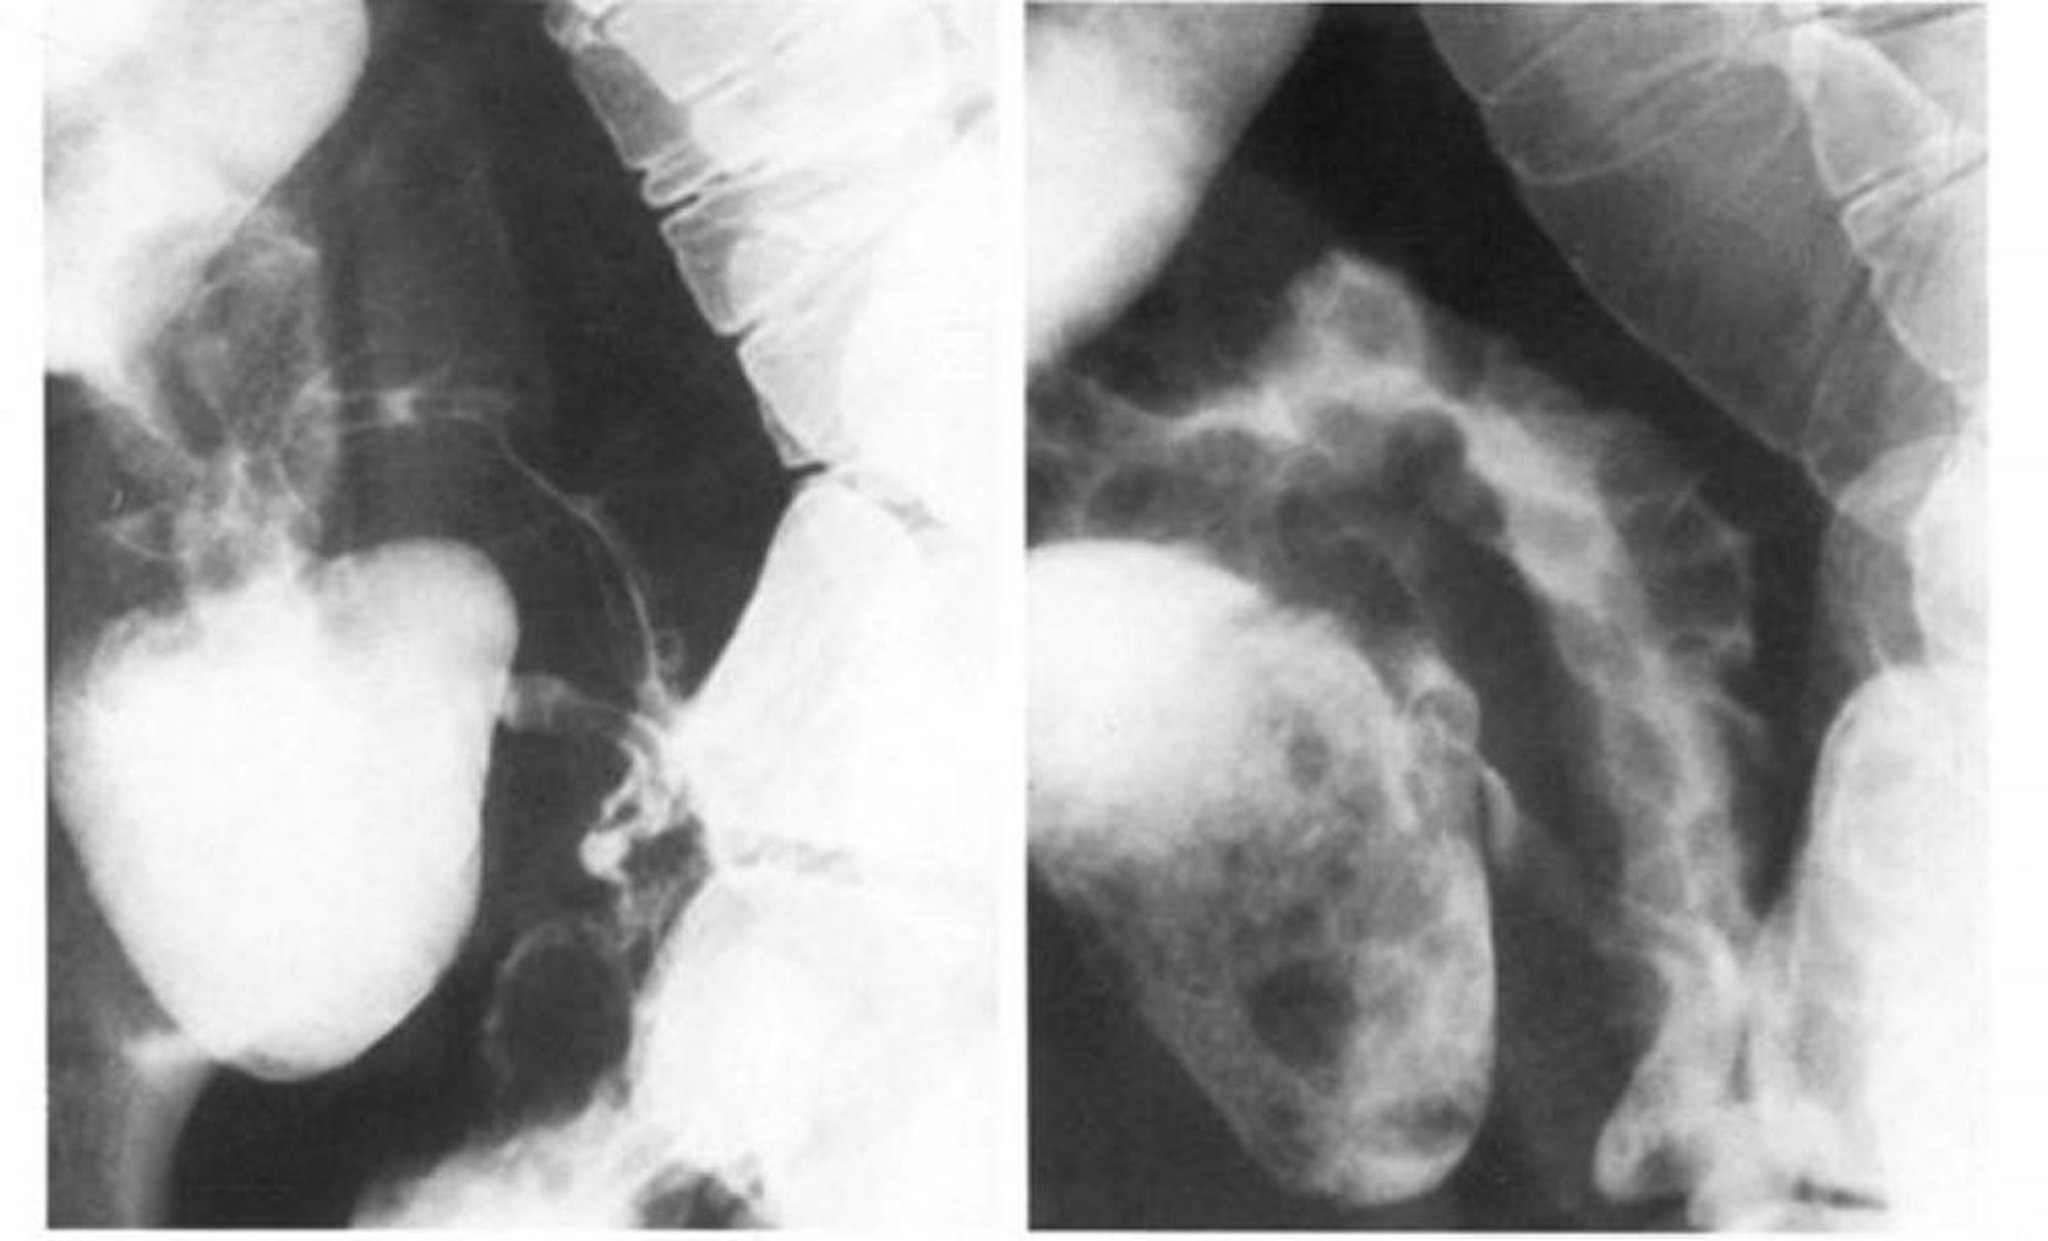

Hình ảnh bên trái cho thấy sự co thắt làm mất đi mô hình đá cuội của đoạn cuối hồi tràng, hình ảnh này được nhìn thấy rõ nhất ở mức cản quang kép trong hình ảnh bên phải.